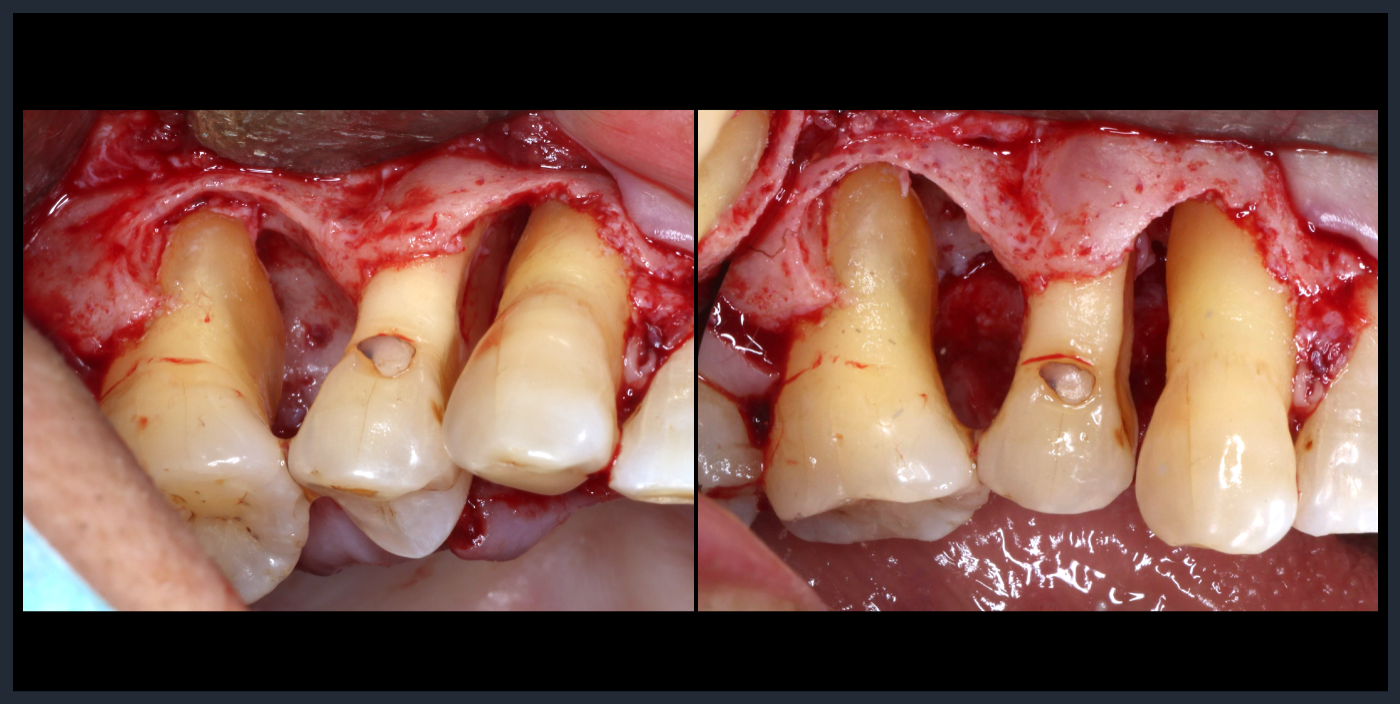

歯周組織再生療法

Periodontal tissue regeneration therapy

Periodontal tissue regeneration therapy

フラップ形成後、多量の縁下歯石。

歯周組織再生療法

Periodontal tissue regeneration therapy

Periodontal tissue regeneration therapy

フラップ形成後、多量の縁下歯石。